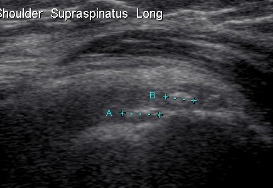

Ultrasound

Ultrasound Calcific TendonitisUltrasound Calcium Supraspinatous